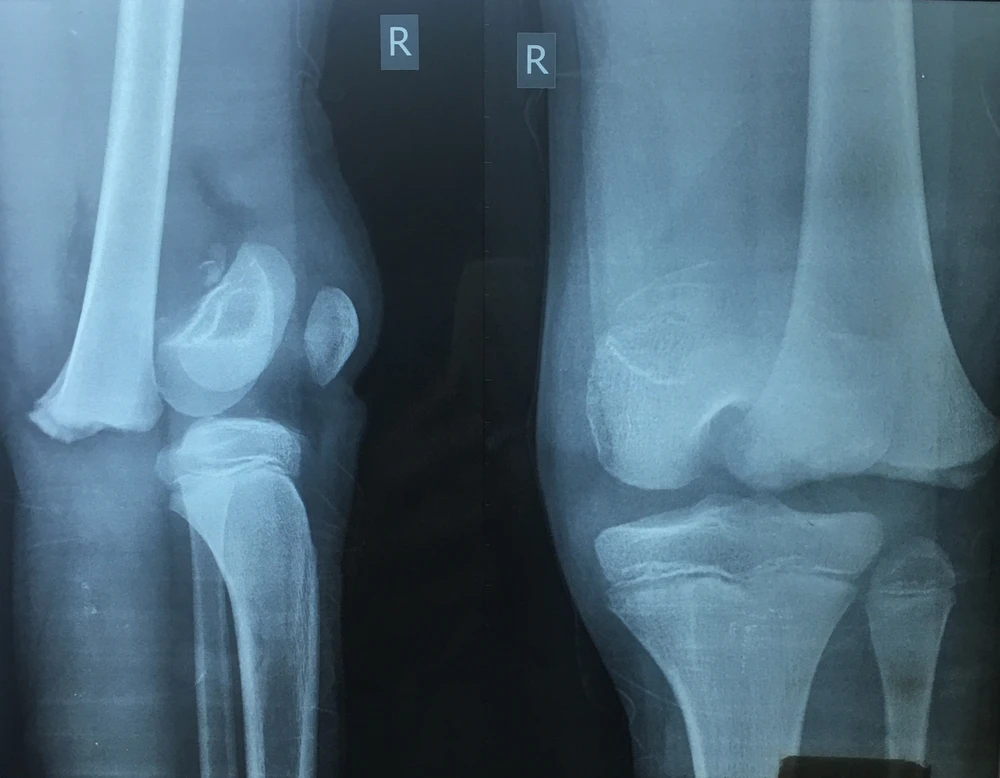

Kết quả chụp X-quang cho thấy chân phải của bệnh nhi ĐAG bị gãy. Ảnh: HÒA KHÁNH

Kết quả chụp X-quang và siêu âm do BV Chấn thương Chỉnh hình TP.HCM thực hiện cho thấy bệnh nhi gãy trật bong sụn tiếp hợp đầu dưới xương đùi và tắc hoàn toàn động mạch khoeo chân phải nên phải phẫu thuật.